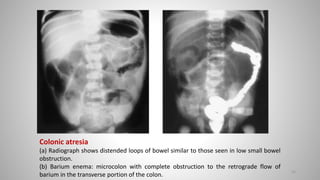

Colonic atresia

(a) Radiograph shows distended loops of bowel similar to those seen in low small bowel

obstruction.

(b) Barium enema: microcolon with complete obstruction to the retrograde flow of

barium in the transverse portion of the colon.